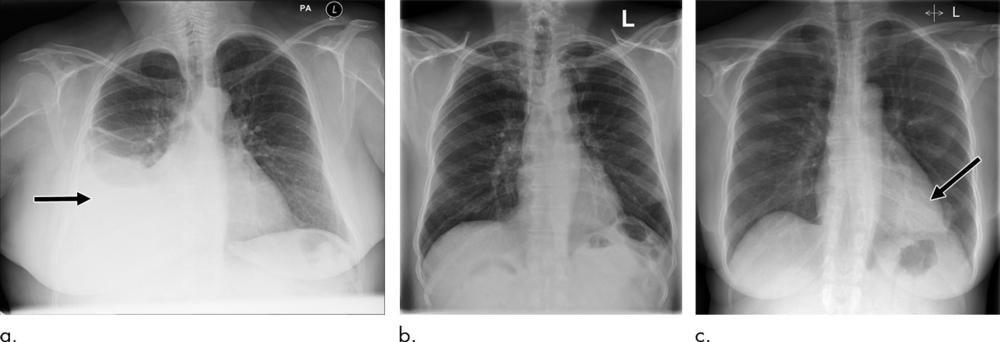

Figure 5. Examples of correctly and incorrectly prioritized radiographs. (a) Radiograph was reported as showing large right pleural effusion (arrow). This was correctly prioritized as urgent. (b) Radiograph reported as showing “lucency at the left apex suspicious for pneumothorax.” This was prioritized as normal. On review by three independent radiologists, the radiograph was unanimously considered to be normal. (c) Radiograph reported as showing consolidation projected behind heart (arrow). The finding was missed by the artificial intelligence system, and the study was incorrectly prioritized as normal.